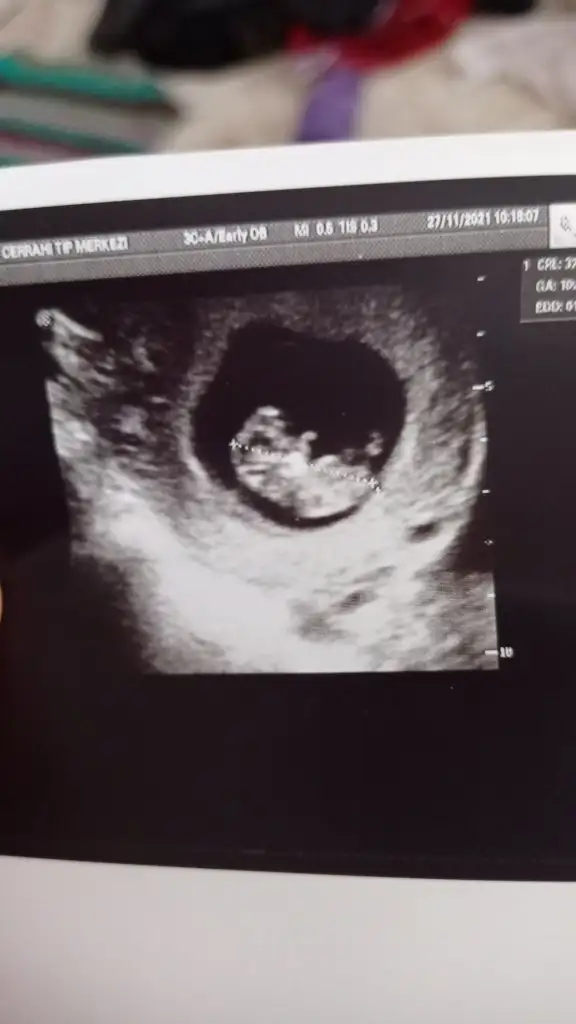

Canım bizde 13 haftalık olduk geldik bakar mısın

Doktor bir şey demedi